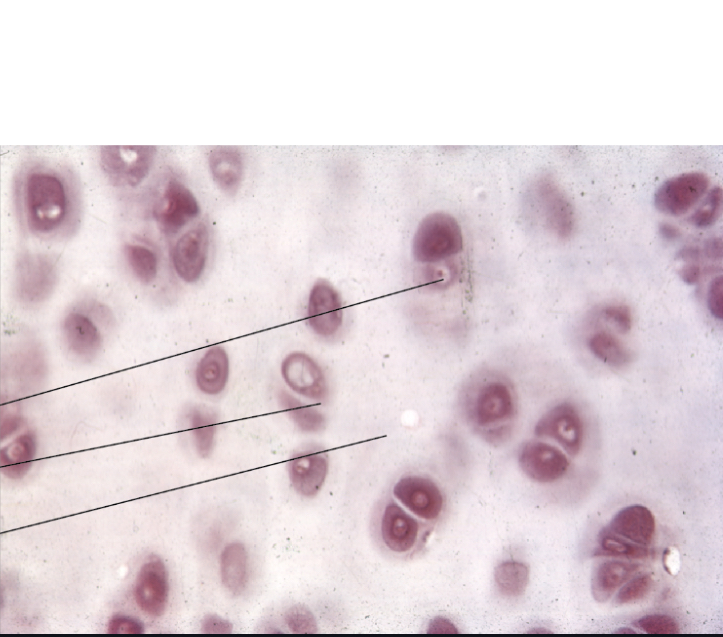

What type of cartilage is this?

Fibrocartilage

Elastic cartilage

Hyaline cartilage